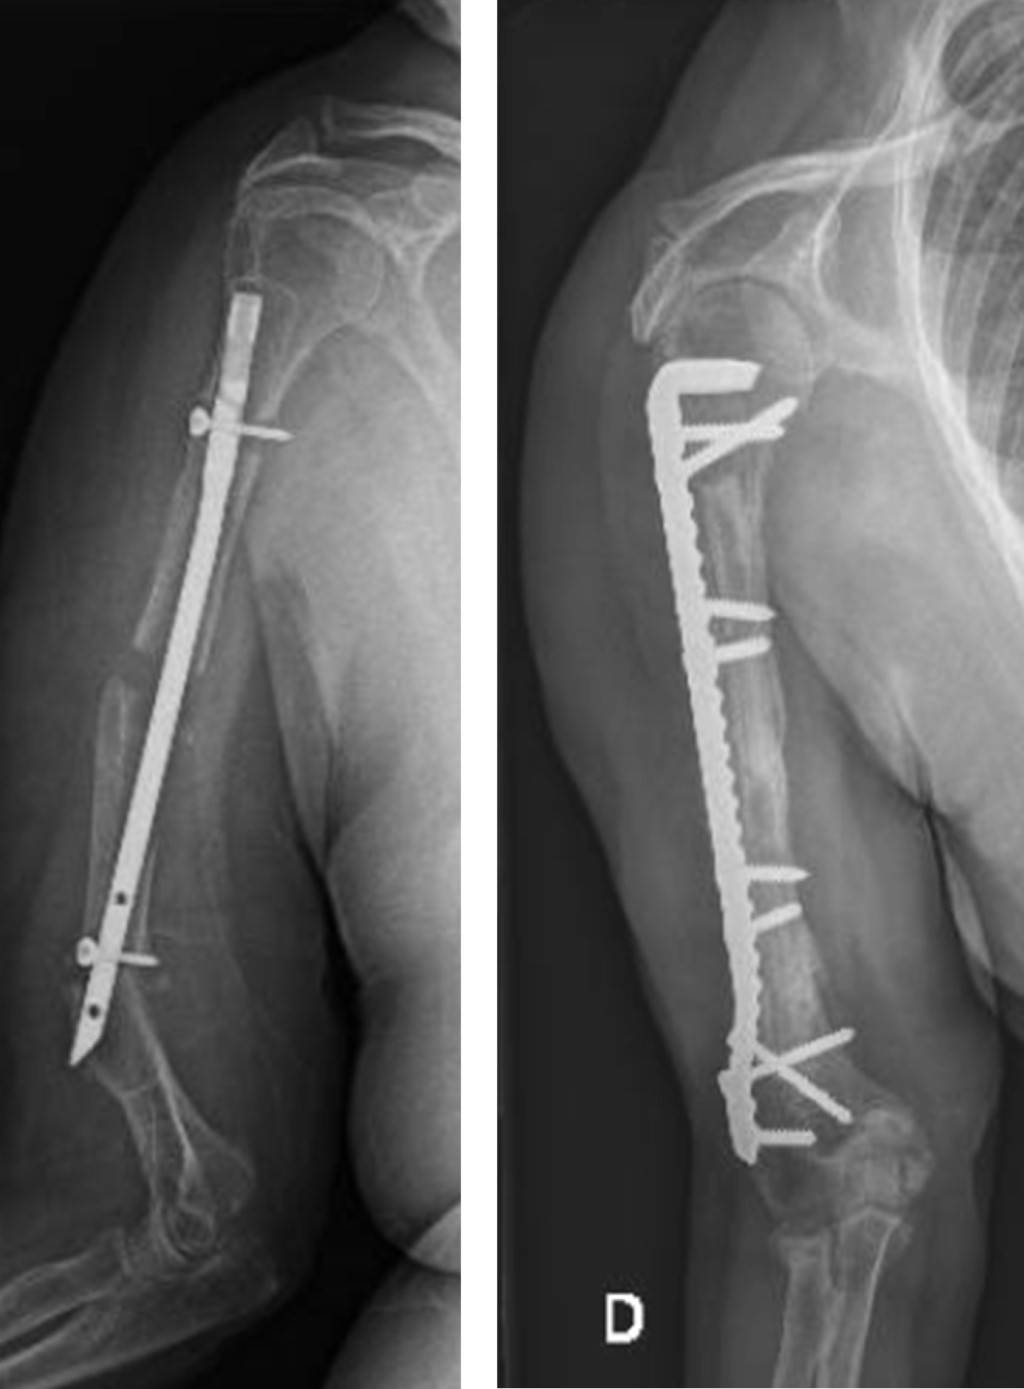

El miembro superior derecho estaba comprometido en nueve pacientes y el izquierdo en 13; el miembro dominante fue el afectado en 10 casos. El tercio proximal de la diáfisis humeral estaba involucrado en ocho pacientes, el tercio medio en otros ocho, el tercio distal en cuatro y dos pacientes presentaban no-consolidaciones segmentarias de la diáfisis humeral (Figura 1). El tiempo desde el trauma inicial hasta el tratamiento definitivo de la no-consolidación promedió 18 meses (rango: 6 a 51). El tratamiento inicial había sido conservador con yeso o brace termoplástico en cuatro pacientes y en 18 el tratamiento inicial fue quirúrgico; 12 pacientes habían tenido una cirugía previa, tres habían tenido dos cirugías previas, dos habían tenido tres cirugías con anterioridad y un paciente había tenido cuatro cirugías previas (Tabla 1). Al momento de realizar la última cirugía, ocho pacientes presentaban un dispositivo endomedular (seis clavos rígidos y dos clavos elásticos), nueve tenían una placa y en un paciente el implante había sido removido. En 16 de estos 17 casos los implantes fueron removidos en la cirugía definitiva; en un caso, que había sido tratado con clavo endomedular, en el cual la fractura evolucionó hacia la no-consolidación, la estabilización definitiva se realizó con una placa puente LCP larga de 3.5 mm, sin remover el clavo endomedular. Al momento de la cirugía definitiva, tres pacientes presentaban infección activa y tres presentaban antecedente de infección previa. Las reconstrucciones en los tres casos con infección activa fueron realizadas en dos etapas, siguiendo la técnica de la membrana inducida por cemento, descrita por Pelissier y colaboradores para reconstrucción de defectos óseos infectados (Figura 2).13

La estabilización definitiva se realizó utilizando clavos placa bloqueados de 4.5 mm en 12 no-consolidaciones (siete localizadas en el tercio proximal de la diáfisis, dos segmentarias y tres del tercio medio de la diáfisis humeral); placas de compresión bloqueadas (LCP) de 4.5 mm en cinco no-consolidaciones (cinco diafisarias y una del tercio proximal de la diáfisis); en el paciente en el que el clavo endomedular no fue removido, se utilizó una placa LCP de 3.5 mm y se utilizaron dos placas en las cuatro no-consolidaciones del tercio distal de la diáfisis humeral. El largo de las placas promedió 21.38 centímetros (rango: 10.88 a 26.2). El número de orificios de las placas promedió 12.56 (rango: 10 a 16) (Tabla 3); en todos los casos en que se utilizó clavos placa bloqueados o placas LCP, se colocaron de manera híbrida, combinando tornillos de compresión a ambos lados de la no-consolidación primero (para comprimir el foco de no-consolidación), seguidos de tornillos bloqueados a continuación. En los tres pacientes que presentaban infección activa se realizó la reconstrucción en dos etapas, utilizando espaciadores de cemento impregnados con antibiótico (gentamicina y dos gramos de vancomicina) en la primera etapa; el espaciador con antibióticos fue colocado paralelo a la no-consolidación en dos casos e intramedular en el tercer caso. El tiempo entre la colocación del espaciador y el segundo tiempo quirúrgico, en el que se realizó la reconstrucción definitiva, fue de tres meses en los tres casos.

Se asoció injerto óseo en todos los casos; en 17 no-consolidaciones solo injerto óseo esponjoso autólogo de cresta ilíaca (16 de cresta ilíaca anterior y uno de cresta ilíaca posterior), en tres casos se utilizó aloinjerto (estructural en uno y triturado en dos) y en dos fueron combinados aloinjerto estructural e injerto óseo esponjoso autólogo de cresta ilíaca anterior (Figura 1). Las tablas de aloinjerto fueron colocadas endomedulares en dos casos (Figura 1); y en uno se colocaron tablas de aloinjerto tanto endomedular como extramedular (Figura 3). En todos los casos se asoció al injerto óseo dos gramos de vancomicina en polvo colocada localmente a nivel de la no-consolidación.

En pacientes con no-consolidación diafisaria de húmero, el uso de fijación interna con placas combinado con injerto autólogo ha evidenciado elevados porcentajes de consolidación y pocas complicaciones.6 Resultados disimiles han sido publicados en no-consolidaciones de húmero tratadas mediante cambio de clavos endomedulares fallidos;19,20,21 mientras que la revisión con placas en no-consolidaciones diafisarias humeral tratadas inicialmente con clavos endomedulares ha demostrado resultados mejores y más predecibles.22,23 Diversas técnicas han sido descritas para mejorar la fijación interna en hueso osteoporótico, incluyendo placas bloqueadas, combinación de implantes, aumento con cemento, la asociación de tablas de aloinjerto o el cambiar tornillos corticales flojos de 4.5 mm por tornillos de esponjosa de 6.5 mm; todas estas técnicas son útiles y cada una tiene ventajas y desventajas.10 En nuestra serie, clavos placa bloqueados de 4.5 mm se utilizaron en no-consolidaciones que afectaban el tercio proximal de la diáfisis (ocho casos), en no-consolidaciones segmentarias (dos casos) y en no-consolidaciones medio-diafisarias en las que se consideró necesario usar implantes con buen anclaje en la cabeza humeral (dos casos). El uso de clavos placa bloqueados es técnicamente demandante, pero tiene la ventaja de permitir mayor agarre y estabilidad proximal, aspecto de gran relevancia en hueso osteoporótico.7 En los 22 casos se utilizaron placas largas, puenteando el área afectada por implantes previos; el uso de placas largas permitió incrementar la resistencia al arranque de los implantes, incrementar su largo de trabajo y flexibilidad.22